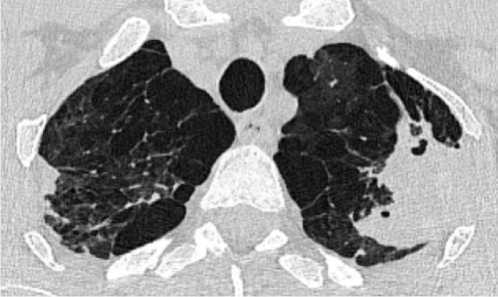

При проведении МСКТ ОГК-В S1 и S2 левого лёгкого субплеврально определяется воздушная полость неправильной формы с толстыми неровными стенками, до 3,5 см в диаметре, небольшим количеством патологического содержимого вдоль стенок. Вдоль заднего контура полости определяется крупная перифокальная зона консолидации, частично сливающаяся со стенкой полости, содержащая в толще единичные мелкие воздушные полости и единичные мелкие кальцинаты. К полости подходят отдельные субсегментарные бронхи, заполненные патологическим содержимым. В апикальных отделах S1 правого лёгкого, субплеврально определяются участки консолидации, с видимыми просветами субсегментарных бронхов – соответствует воспалительным изменениям. В обоих лёгких, в том числе вдоль междолевой плевры, определяются многочисленные мелкие очаги. Отмечаются выраженные эмфизематозные изменения обоих лёгких в виде парасептальной и буллёзной эмфиземы (рис. 1).

Рисунок 1. Аксиальные срезы КТ органов грудной клетки, легочное окно: а – S1 и S2 левого лёгкого, субплеврально определяется воздушная полость неправильной формы с толстыми неровными стенками; б – в обоих лёгких определяются многочисленные мелкие очаги, выраженные эмфизематозные изменения обоих лёгких в виде эмфиземы

Figure 1. Axial CT scans of the chest organs, pulmonary window: a – S1 and S2 of the left lung, an irregularly shaped air cavity with thick uneven walls is determined subpleurally; б – numerous small foci are detected in both lungs, pronounced emphysematous changes in both lungs in the form of emphysema